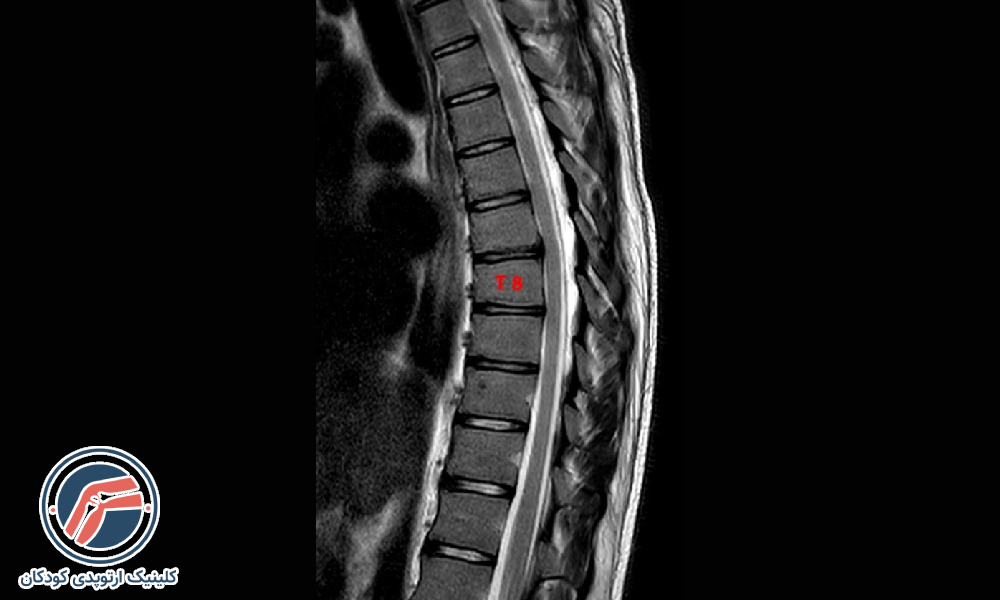

- تصویربرداری: تصویربرداری به مشخصشدن دقیقتر انحنا و میزان قوس کمر کمک میکند. معمولاً پزشکان کودکانی که دارای کیفوز خفیف هستند را بهدقت تحتنظر میگیرند و در دورههای ۶ ماهه از ستون فقرات آنها بهوسیله اشعهایکس یا MRI تصویربرداری میکنند. در بزرگسالان علاوه بر تصویربرداری ممکن است که به آزمایش خون و آزمایش تراکم استخوان نیز برای تشخیص دقیقتر نیاز باشد.